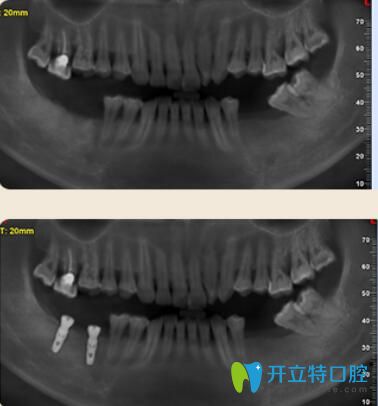

案例二:多顆牙齒缺失的胡先生種植牙案例

胡先生年齡不是特別大,但是已經(jīng)缺牙多顆,不僅影響日常飲食,對發(fā)音也有一定的影響。聽朋友說好佰年口腔的數(shù)字化種植技術(shù)很先進(jìn)的,于是來到了好佰年。

多顆牙齒缺失的胡先生種植牙案例

因為胡先生對疼痛非常敏感。所以在種植時候結(jié)合睡眠技術(shù),種牙過程中沒有任何的不適和疼痛感,半小時后種好牙齒,隨便吃,再也不用擔(dān)心吃硬東西了!

東莞好佰年口腔多顆牙種植案例